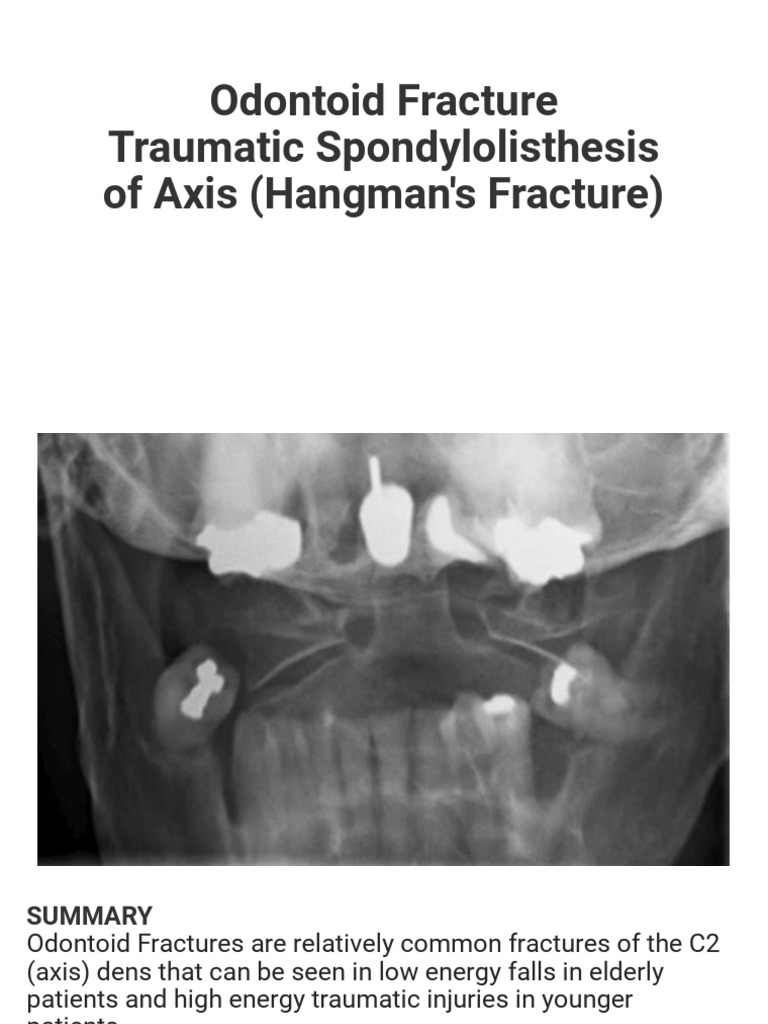

Odontoid Fracture | PDF | Vertebral Column | Vertebra, image size:1998x704

Odontoid Fracture | PDF | Vertebral Column | Vertebra